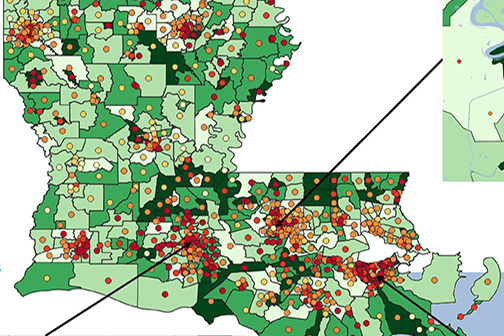

LSU Health New Orleans LA Tumor Registry Releases 6th Census Tract Cancer Incidence Report

LSU Health New Orleans Louisiana Tumor Registry (LTR) has published the sixth report of statewide cancer incidence rates by census tract. The publication, which reports 2010-2019 combined cancer incidence data, found that 81% of the census tracts in Louisiana met publication criteria for all cancers combined. More

Proof-of-Concept Demonstration Recommends Continuous Air Monitoring & Other Precautionary Practices in St. John Parish

A small monitoring demonstration around the Denka facility in St. John the Baptist Parish conducted by LSU Health New Orleans School of Public Health reports detectable chloroprene in two air samples and metabolites indicating exposure to volatile organic compounds in most urine samples, even when the plant was not operating. More

LSU Health New Orleans LA Tumor Registry Releases 5th Census Tract Cancer Incidence Report

LSU Health New Orleans Louisiana Tumor Registry (LTR) has published the fifth report of statewide cancer incidence rates by census tract. The publication, which reports 2009-2018 combined cancer incidence data, found that 81% of the census tracts in Louisiana met publication criteria for all cancers combined. For specific cancer types, fewer census tracts met the criteria. For the Louisiana census tracts meeting the criteria, the incidence rates for all cancers combined and for specific cancer types were compared with the corresponding rates for the entire state. More

Latest Cancer in LA Volume Contains New Incidence & Mortality Tables for Industrial Corridor

LSU Health New Orleans School of Public Health’s Louisiana Tumor Registry has published the latest report on cancer incidence and mortality in Louisiana – Cancer in Louisiana 2014-2018 (Volume 36). More